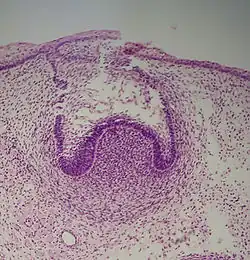

Die Zahnbildung beginnt mit einer Verdickung des Epithels der Mundhöhle, die als Zahnleiste bezeichnet wird. Bei der weiteren Entwicklung der Zähne unterscheidet man folgende Stadien: Knospe, Kappe, Glocke und die Reife. Die Einteilung ist der Versuch, kontinuierlich ablaufende Veränderungen zu kategorisieren; die genaue Zuordnung ist im Einzelfall oft schwierig (Cate 1998:81[1]). Die Bestimmung wird zusätzlich durch verschiedene histologische Schnitte erschwert.

Knospenstadium

Dieser Abschnitt ist durch das Erscheinen der Zahnknospe ohne klare Anordnung der Zellen gekennzeichnet. Technisch gesehen beginnt das Stadium, wenn Epithelzellen aus der Zahnleiste in das Ektomesenchym des Kiefers vordringen (Cate 1998:82[1]). Die Zahnknospe selbst ist die Gruppe von Zellen am Ende der dentalen Lamina.

Kappenstadium

Die ersten Zeichen einer Anordnung von Zellen in der Zahnknospe gibt es im Kappenstadium. Eine kleine Gruppe ektomesenchymaler Zellen beendet die Produktion extrazellulärer Substanzen, was zur Bildung der Zahnpapille führt. Zu diesem Zeitpunkt wächst die Zahnknospe rund um die ektomesenchymale Anordnung, nimmt die Form einer Kappe an und wird zum Zahnschmelzorgan. Ein Niederschlag ektomesenchymaler Zellen, den man als Zahnfollikel bezeichnet, umgibt das Zahnschmelzorgan und begrenzt die Papille. Das Zahnschmelzorgan produziert schließlich den Zahnschmelz, die Papille das Dentin und der Follikel alle unterstützenden Strukturen eines Zahns (Cate 1998:84[1]).